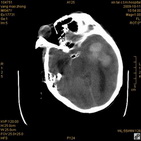

病人杨XX,男,青云街道办事处路踏泉村,住院号51666,CT号:104770。病人因“高血压脑出血”在新泰市人民医院住院治疗5天,治疗效果不佳转入我院,复查CT示左基底节血肿,病人昏迷状态,给予血肿清除术,术后2天复查CT,血肿完全清除,病人恢复好,治疗效果满意。附病人术前术后CT片资料如下。

术前CT

术前CT1 术前CT2 术前CT3 术前CT4